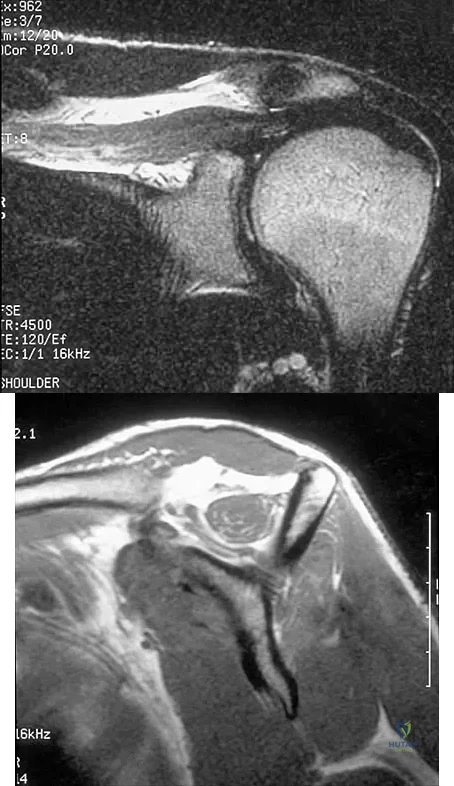

Figures 36a and 36b show the MRI scans of a patient who has shoulder weakness. What is the most likely diagnosis?

Explanation